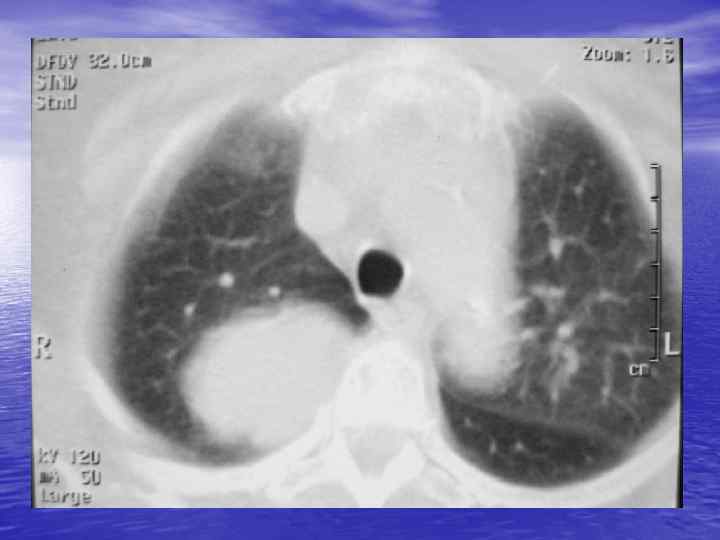

Денситометрический анализ Определение основных видов патологических образований: - обызвествленных - мягкотканных - жидкостных - жиросодержащих - воздухсодержащих

Электронные окна üОкном (Window) называют определенную часть шкалы Хаунсфилда, которой соответствует перепад величины яркости экрана от белого до черного. üШирина окна (Window Width, WW) — это величина разности наибольшего и наименьшего коэффициента ослабления, отображаемых данным перепадом яркости от белого до черного цвета. üУровень окна (Window Level, WL) — это величина коэффициента ослабления, соответствующая середине окна. Изменение уровня окна позволяет перемещать его в сторону больших или меньших значений чисел Хаунсфилда.

Характеристика основных электронных окон Электронное окно WINDOW Уровень окна Ширина окна Мягкотканное Soft +40 500 Легочное Lung -800 1000 Плевральное Pleural -650 -150 1500 -2000 Костное Вone +150+350 1000 -2000

Преимущества спиральной КТ: ü Возможность проведения исследования с болюсным ü ü ü ü ü контрастированием Высокая разрешающая способность; Высокая скорость исследования; Получение высококачественных изображений костных структур; Возможность обследования всего тела; Возможность проведения исследования больных под наркозом; Возможность детальной оценки состояния крупных и периферических сосудов в условиях искусственного контрастирования; Высокая информативность метода при черепномозговых травмах в остром периоде; Ранняя диагностика ишемических и геморрагических инсультов; Метод выбора для диагностики заболеваний легких; Планирование лучевой терапии.